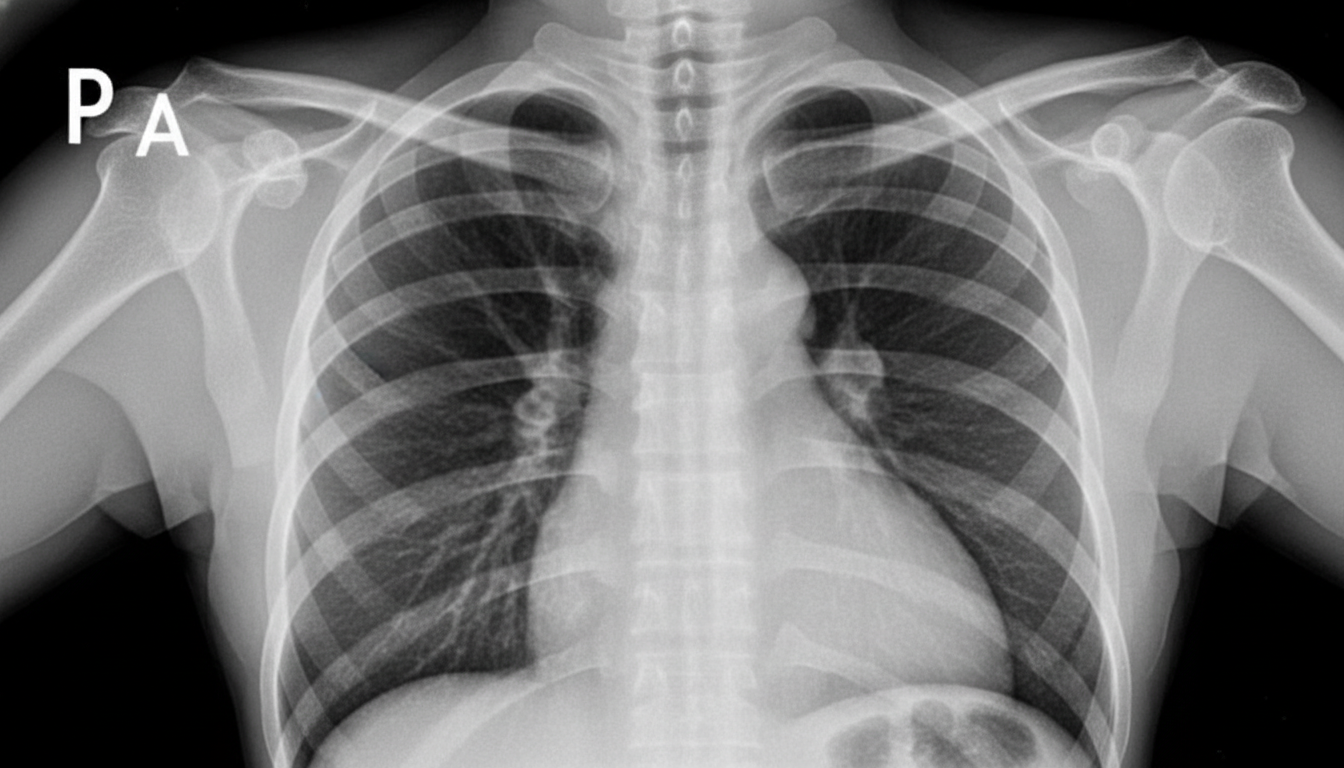

A 75-year-old over-weight gentleman with a long history of uncontrolled hypertension, diabetes, smoking and obesity is presenting to his primary care physician with a chief complaint of increased difficulty climbing stairs and the need to sleep propped up by an increasing number of pillows at night. On physical examination the patient has an extra heart sound just before S1 heard best over the cardiac apex and clear lung fields. The EKG and chest x-ray are attached (Figures A and B respectively). What is the largest contributor to this patient's symptoms?

A 64-year-old man who recently immigrated to the United States from Haiti comes to the physician because of a 3-week history of progressively worsening exertional dyspnea and fatigue. For the past few days, he has also had difficulty lying flat due to trouble breathing. Over the past year, he has had intermittent fever, night sweats, and cough but he has not been seen by a physician for evaluation of these symptoms. His temperature is 37.8°C (100°F). An x-ray of the chest is shown. Further evaluation of this patient is most likely to show which of the following findings?